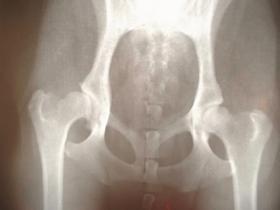

1. 骨の問題です。股関節はふとともの骨(大腿骨)と骨盤で構成されております。一番多いのは、股関節の変形です。股関節の変形とは、関節の軟骨が割れていたり、削れている状態です。

股関節は骨盤と大腿骨で構成される関節で、丸い大腿骨頭が臼のような寛骨臼の中にはまりこんでいる作りになります。股関節痛の原因には、筋肉疾患、内臓疾患など多岐にわたります。股関節の痛みは過去の事故によるものや生活パターンのクセによるものもあります。

レントゲンやMRIによって、股関節内の問題がないか確認する必要があります。股関節内の問題としては、股関節内に骨の棘ができたり、軟骨が擦り減る状態です。レントゲンの判断がすべてではありません。股関節がすりへっていても痛みがでない方はいます。自分がどのような状態かその方自身がしっかり見極める必要があります。